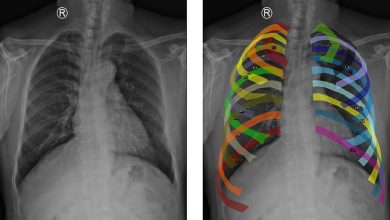

Investigadores gaditanos crean un modelo inteligente que mejora el diagnóstico temprano de enfermedades pulmonares

diagnóstico pulmonar